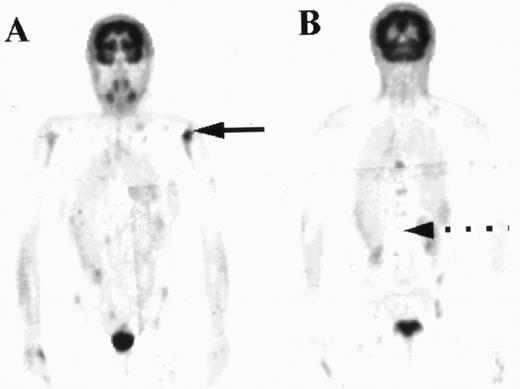

PET images of a patient with areas of focal increased uptake in marrow, most notably in the left humerus (solid arrow, A) and in the thoracic spine (B). The marrow was not diffusely abnormal and much of the axial skeleton exhibited FDG uptake less than in liver (broken arrow).

All four patients who had focal marrow disease on the PET scan but histologically normal iliac crest marrow had normal FDG uptake at the site of the biopsy. In that respect these patients could be classed as concordant. In one of these patients subsequent biopsy of a “hot spot” localized within the left humeral head confirmed nodular sclerosing HD in the marrow (Fig 4). The other 3 patients did not have additional biopsies, but the 2 patients with high-grade NHL had other evidence of stage IV disease, with pulmonary lymphoma deposits shown by PET and CT.